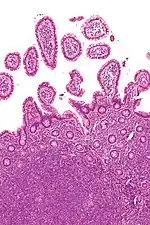

![]() Мікрофотографія негоджкінської лімфоми. Мікрофотографія негоджкінської лімфоми. | |